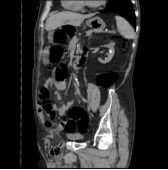

MPR图像:多方位观察大肠病变的三维形态及与周围的毗邻关系。

冠状位

斜冠状位